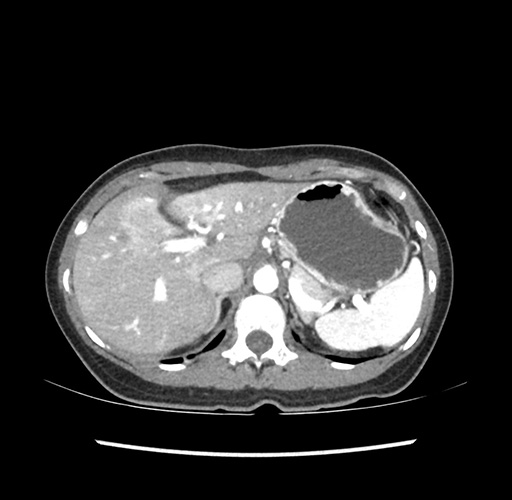

Imaging Analysis

Look through the patient's CT scan to identify any areas of concern for the necessary procedure.

Based on your CT findings, which issue(s) would give reason for "planned slowing down moment(s)" in this case?